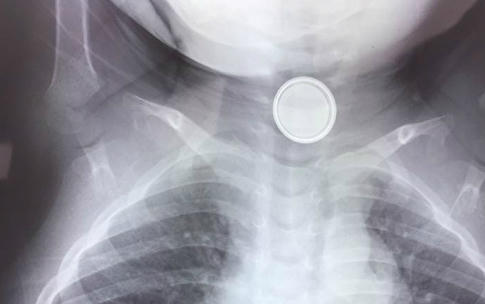

Trước đó, cháu bé được người nhà đưa vào viện cấp cứu trong tình trạng khó thở, ăn khó nuốt. Sau khi chụp X-Quang đã phát hiện một dị vật hình tròn nằm trong thực quản bệnh nhi.

Ngay lập tức các bác sĩ Bệnh viện Hữu nghị Việt Nam - Cuba Đồng đã tiến hành hội chẩn và quyết định nội soi gắp dị vật cho cháu. Kết quả kíp mổ đã lấy ra từ thực quản bé một cục pin điện tử hình tròn, đường kính 1 cm.